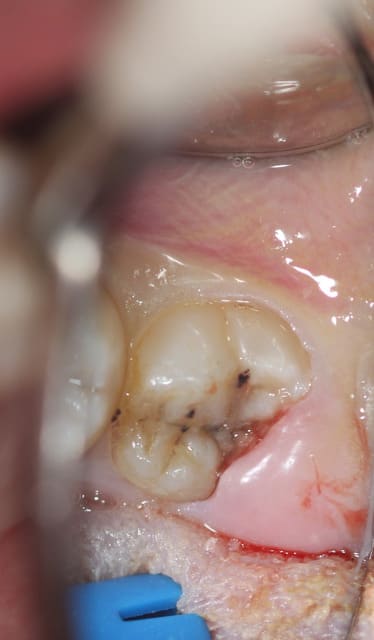

jeune patiente de 18ans avec sa 38completement dégagée de l'os mais persistance d'un capuchon muqueux régulièrement inflammatoire et douloureux... pour conserver la dent... que faire? un distal-wadge (pas sur de l'orthographe) une suppression du capuchon distal... j'en ai jamais fait... dois je procéder comme pour une élongation coronaire? ou incision en quartier d'orange???

cela dit, vu les débuts d'attaques carieuses sur cette dent, je pense que ton patient ne finira pas sa vie avec cette 8. J'opterais probablement pour son élimination.

voila finalement on a opter pour la conservation de la dent...

Décapuchonné à la lame froide saignement modéré (infiltration d’anesthésie adrénalinée tout autours de la couronne... Un point de suture dix jours après compo. conseils d’hygiène.

la patiente est contente d'avoir conserver sa dent...